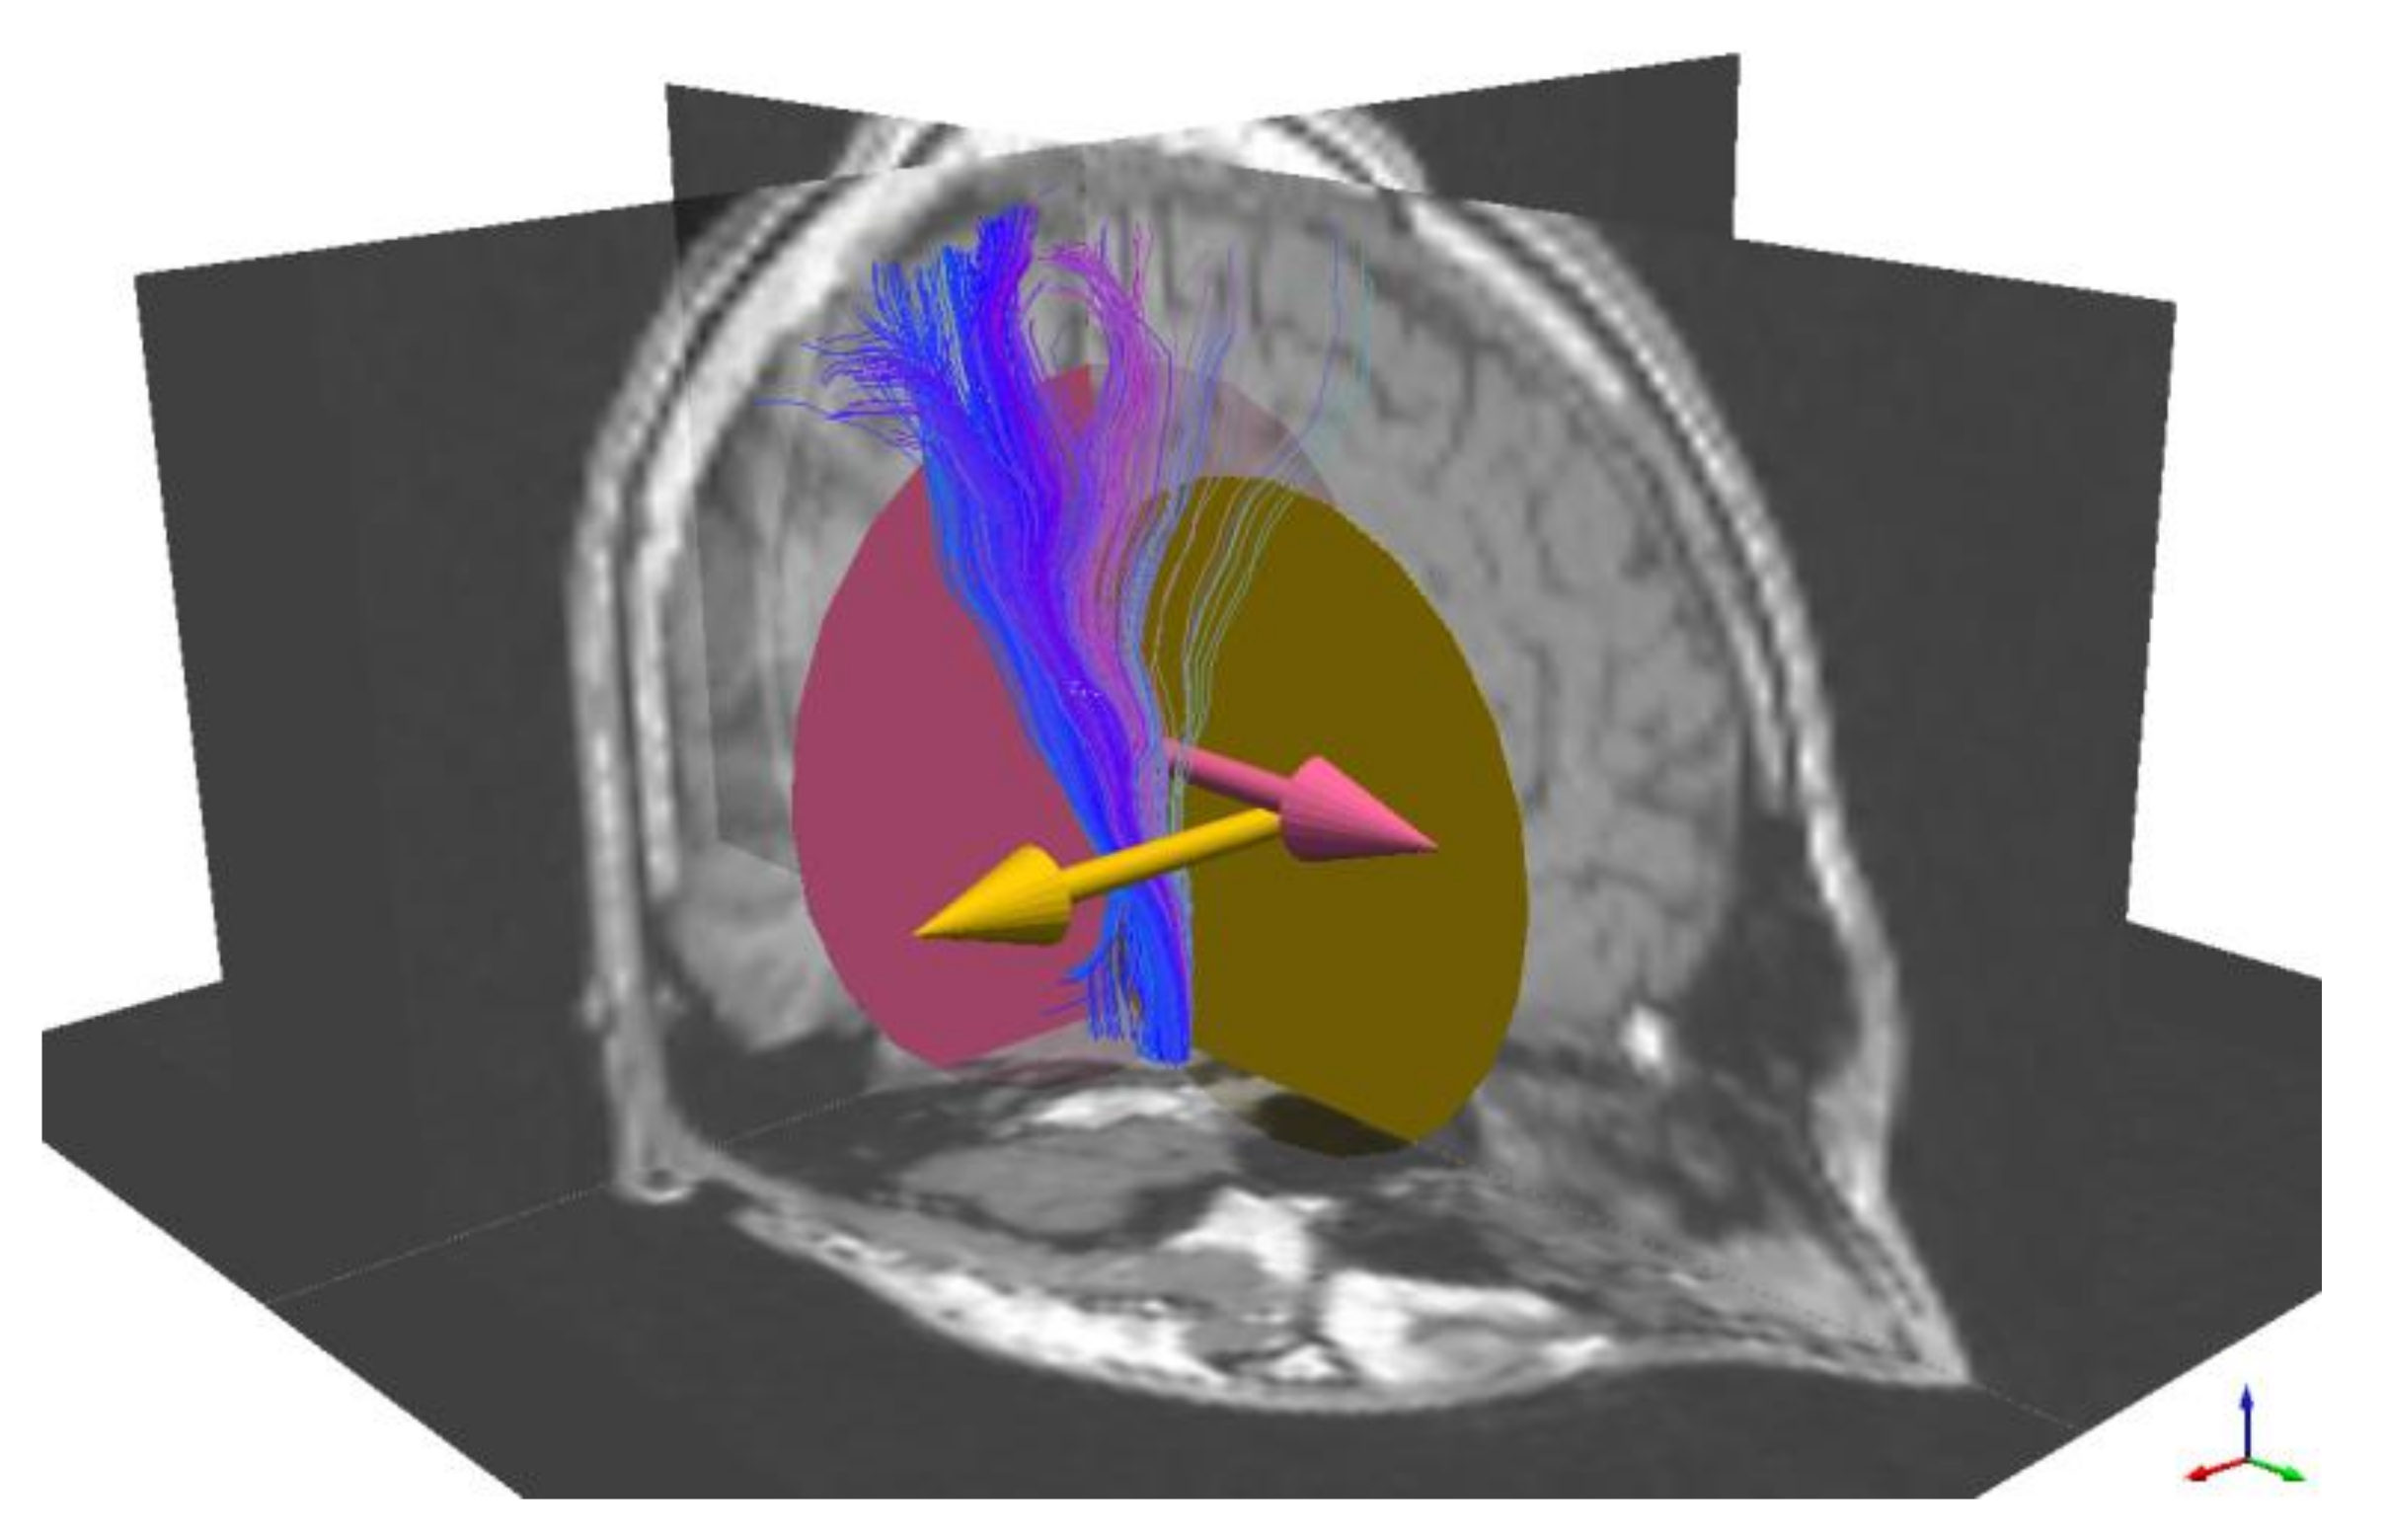

3.1. The Corticospinal Tract

2.7. Seed Regions and Selection of White Matter Tracts